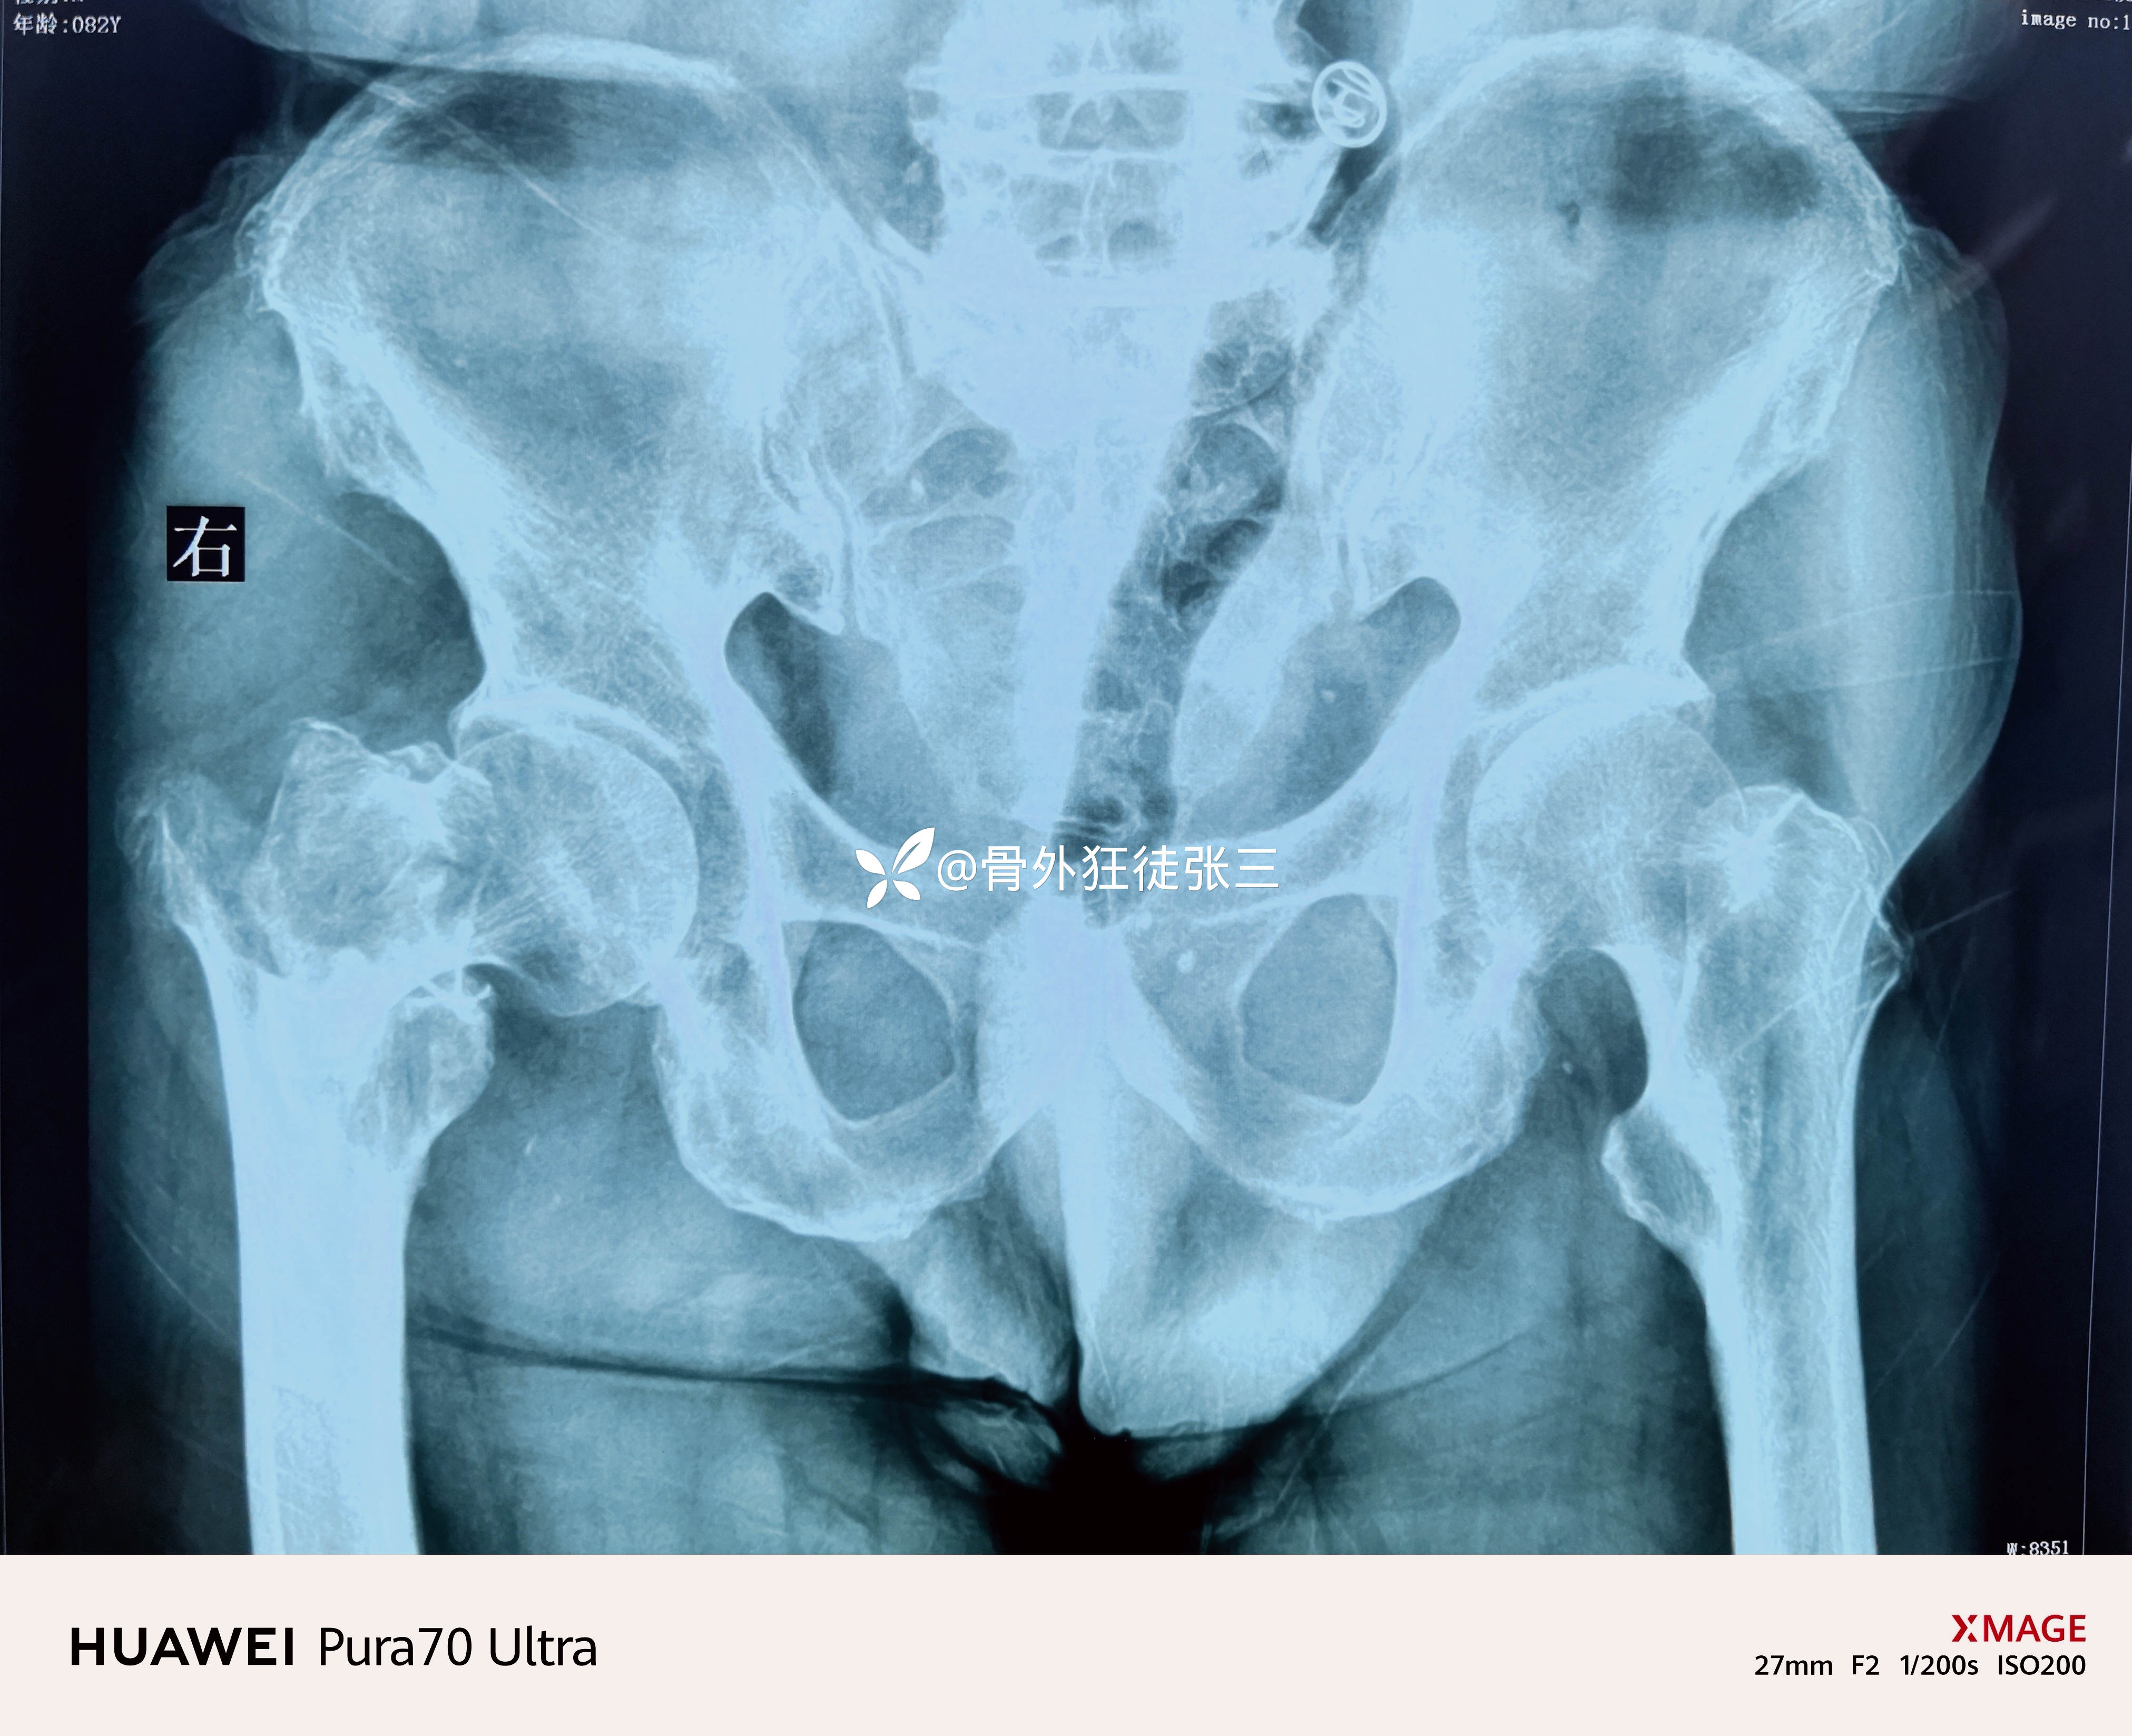

曹谦湘潭市中医院 等 2 位达人已点赞患者性别:男

患者年龄:82岁

主诉:摔伤右髋部致肿痛、畸形、活动受限5天。

右股骨转子间骨折